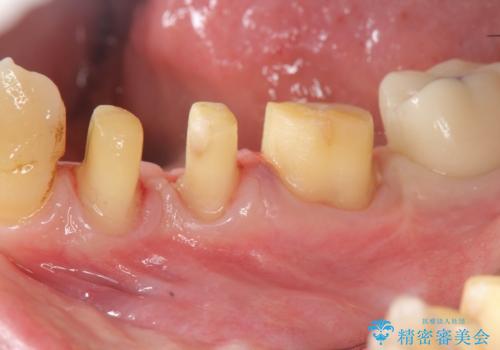

歯周病再生治療と歯周ポケット除去 歯周外科手術

- 30代女性

- 他院で歯周病を指摘され、様子見ではなく根本的な治療はないか?とご相談に来院されました。

重度の歯周病で再生療法の適応ではない最後方臼歯は抜去行い、インプラント治療、

がたつきの強い天然歯を矯正治療で整えたのち、再生治療、歯周ポケットを除去する歯周外科手術を行いました。

歯周病の問題が解決したのち、歯の揺れを抑えるべくセラミッククラウンで連結補綴をおこなっています。